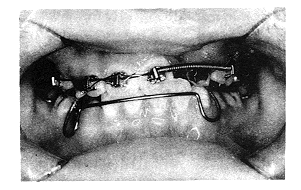

由于唇腭裂患者多数存在上颌宽度发育不足,因而矫治中需行不同程度的扩弓治疗。本组有8例采用了上颌四角腭弓(quid-helix)扩弓技术(图1),1例采用上颌快速螺簧扩弓器及前方牵引装置,3例采用上颌活动矫治器附分裂簧改善后牙反。扩弓病例约占60%。术前正畸疗程最短3个月,最长13个月。术前正畸排齐上前牙后拍X线片,当恒尖牙牙根形成达2/3时行牙槽突植骨术。供骨区除1例采用颏部髓质骨外,均采用髂骨髓质骨。20例植骨手术均成功,伤口I期愈合,X线片显示骨密度正常。对于畸形严重的患者,术后3~6个月后开始正畸,全部采用方丝弓、细丝弓矫治技术,直到恒牙全部建,建立正常覆覆盖关系,矫治效果满意。

图1 上颌四角腭弓开展上牙弓宽度